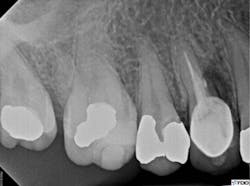

The access cavity and canal walls were examined for fracture or perforation. While a fracture was not observed, a perforation was visualized at the apical extent of the post preparation in the lingual canal. Conventional re-treatment of both the buccal and lingual canals was completed. Careful attention to the irrigation protocol was made in order to prevent extrusion of irrigating solutions outside of the perforated root. The buccal canal was obturated to the canal orifice, and the lingual canal was packed apical to the perforation. A small piece of absorbable collagen material (OraTape, Salvin Dental) was packed into the perforation until a matrix was formed that would keep the repair material confined to the root. The perforation and coronal third of the lingual canal were filled with mineral trioxide aggregate (MTA) (figure 4). The occlusal access was sealed with cotton and Cavit temporary filling material (3M ESPE). The final treatment radiograph shows re-treatment and repair (figure 5).

Figure 4: MTA used to fill the perforation and coronal third of the lingual canal

Figure 5: Final radiograph showing re-treatment and repair